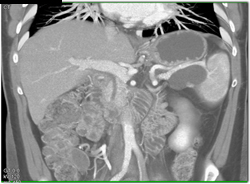

Pseudocyst